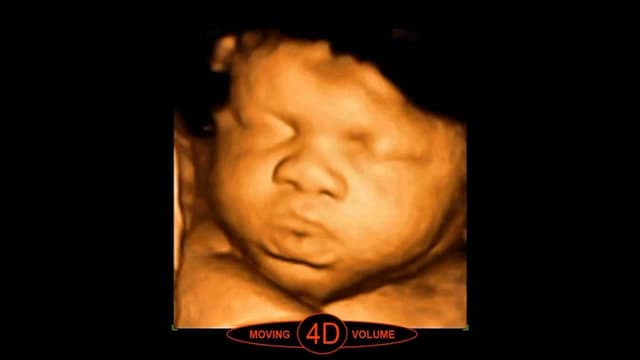

Siêu âm thai 4D và những điều mẹ bầu nên nắm rõ

Siêu âm thai 4D là phương pháp chẩn đoán hình ảnh ra đời dựa trên cơ sở của phương pháp siêu âm 2D và 3D. Do đó, siêu âm 4D hội tụ đầy đủ những ưu điểm tuyệt vời của các kỹ thuật siêu âm cũ. Vì vậy, mẹ bầu có thể quan sát được […]